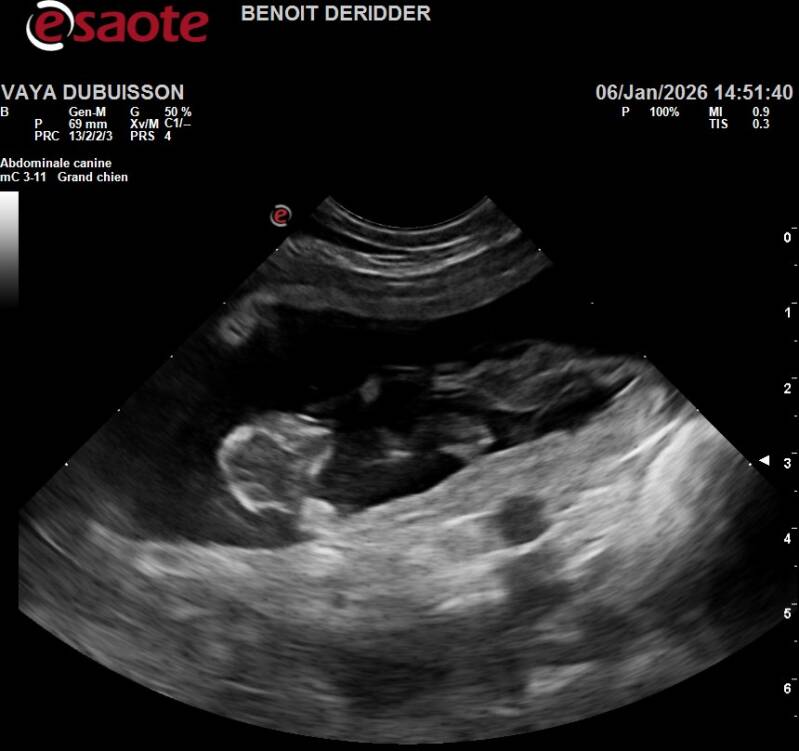

Ce 06/01/2026, je suis allée chez le veto pour une échographie afin de confirmer la gestation de Vayana mais à coup sûr, j'en étais convaincue parce que Vasco & Vayana c'est magique, je dirai même plus une alchimie, ils ne leur suffit qu'un seul accouplement pour que la magie opère..

Ça y est, Benoît commence à passer sur le ventre de Vayana et nous pouvons apercevoir sur l'écran jouxtant en hauteur de la table quelque chose ou ressemble à ... Oui oui dit-il avec un sourire joviale, Vayana a remis ça, on en compte approximativement 7 mais connaissant la demoiselle, nous ne serions pas surpris d'en avoir 10...